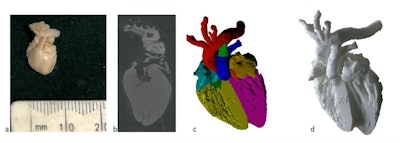

3D printing techniques can be an advantage in legal cases, and we can now print out 3D models to help parents, the police, and the courts and even juries to explain quite what has happened to the child in that setting.

Overall, 3D printing is now a fairly cheap and reproducible way of showing imaging data in a simple and easily understandable way. We use 3D printing within our institution mainly for educational purposes (see figure). We have printed a femur with a bone abnormality and a skull with a fracture to show parents and others what these look like.

I think we will use 3D printing much more as an educational tool in the future, particularly in teaching anatomy to medical students. The main limitations are the cost of printing, which is coming down all the time (based on the material you choose to print, it is currently around 10 to 50 pounds [11 to 57 euros] per case) and the time it takes to print; a detailed model with high resolution can take several hours to print. These factors are likely to improve with increasing use and accessibility.